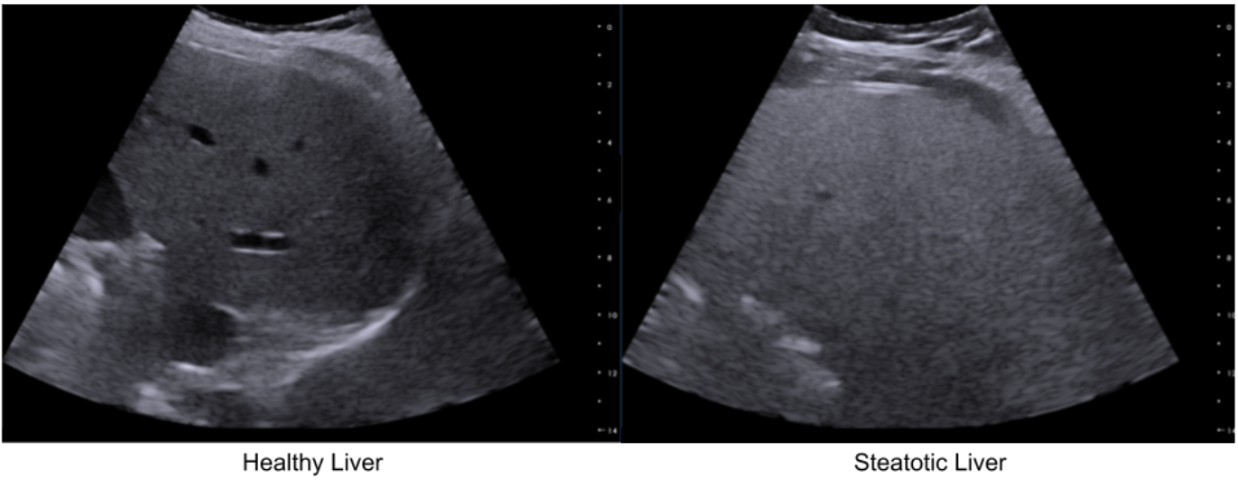

Quantifying steatosis in the liver is the first step in the diagnosis of MASLD and primarily uses non-invasive ultrasound. Initially visual (qualitative), the assessment of fat in the liver has benefited from the development of quantitative ultrasound (QUS) which now offers objective measurements of steatosis-related parameters, surpassing subjective visual assessments.

Increased intracellular fat elevates the backscattering coefficient (BSC), making the liver appear brighter (“bright liver”). Fat also causes higher attenuation (ATT), i.e. signal loss and posterior shadowing, and decreases the speed of sound (SOS) as lipid (fat) medium is a slower medium than healthy (aqueous) liver tissues.